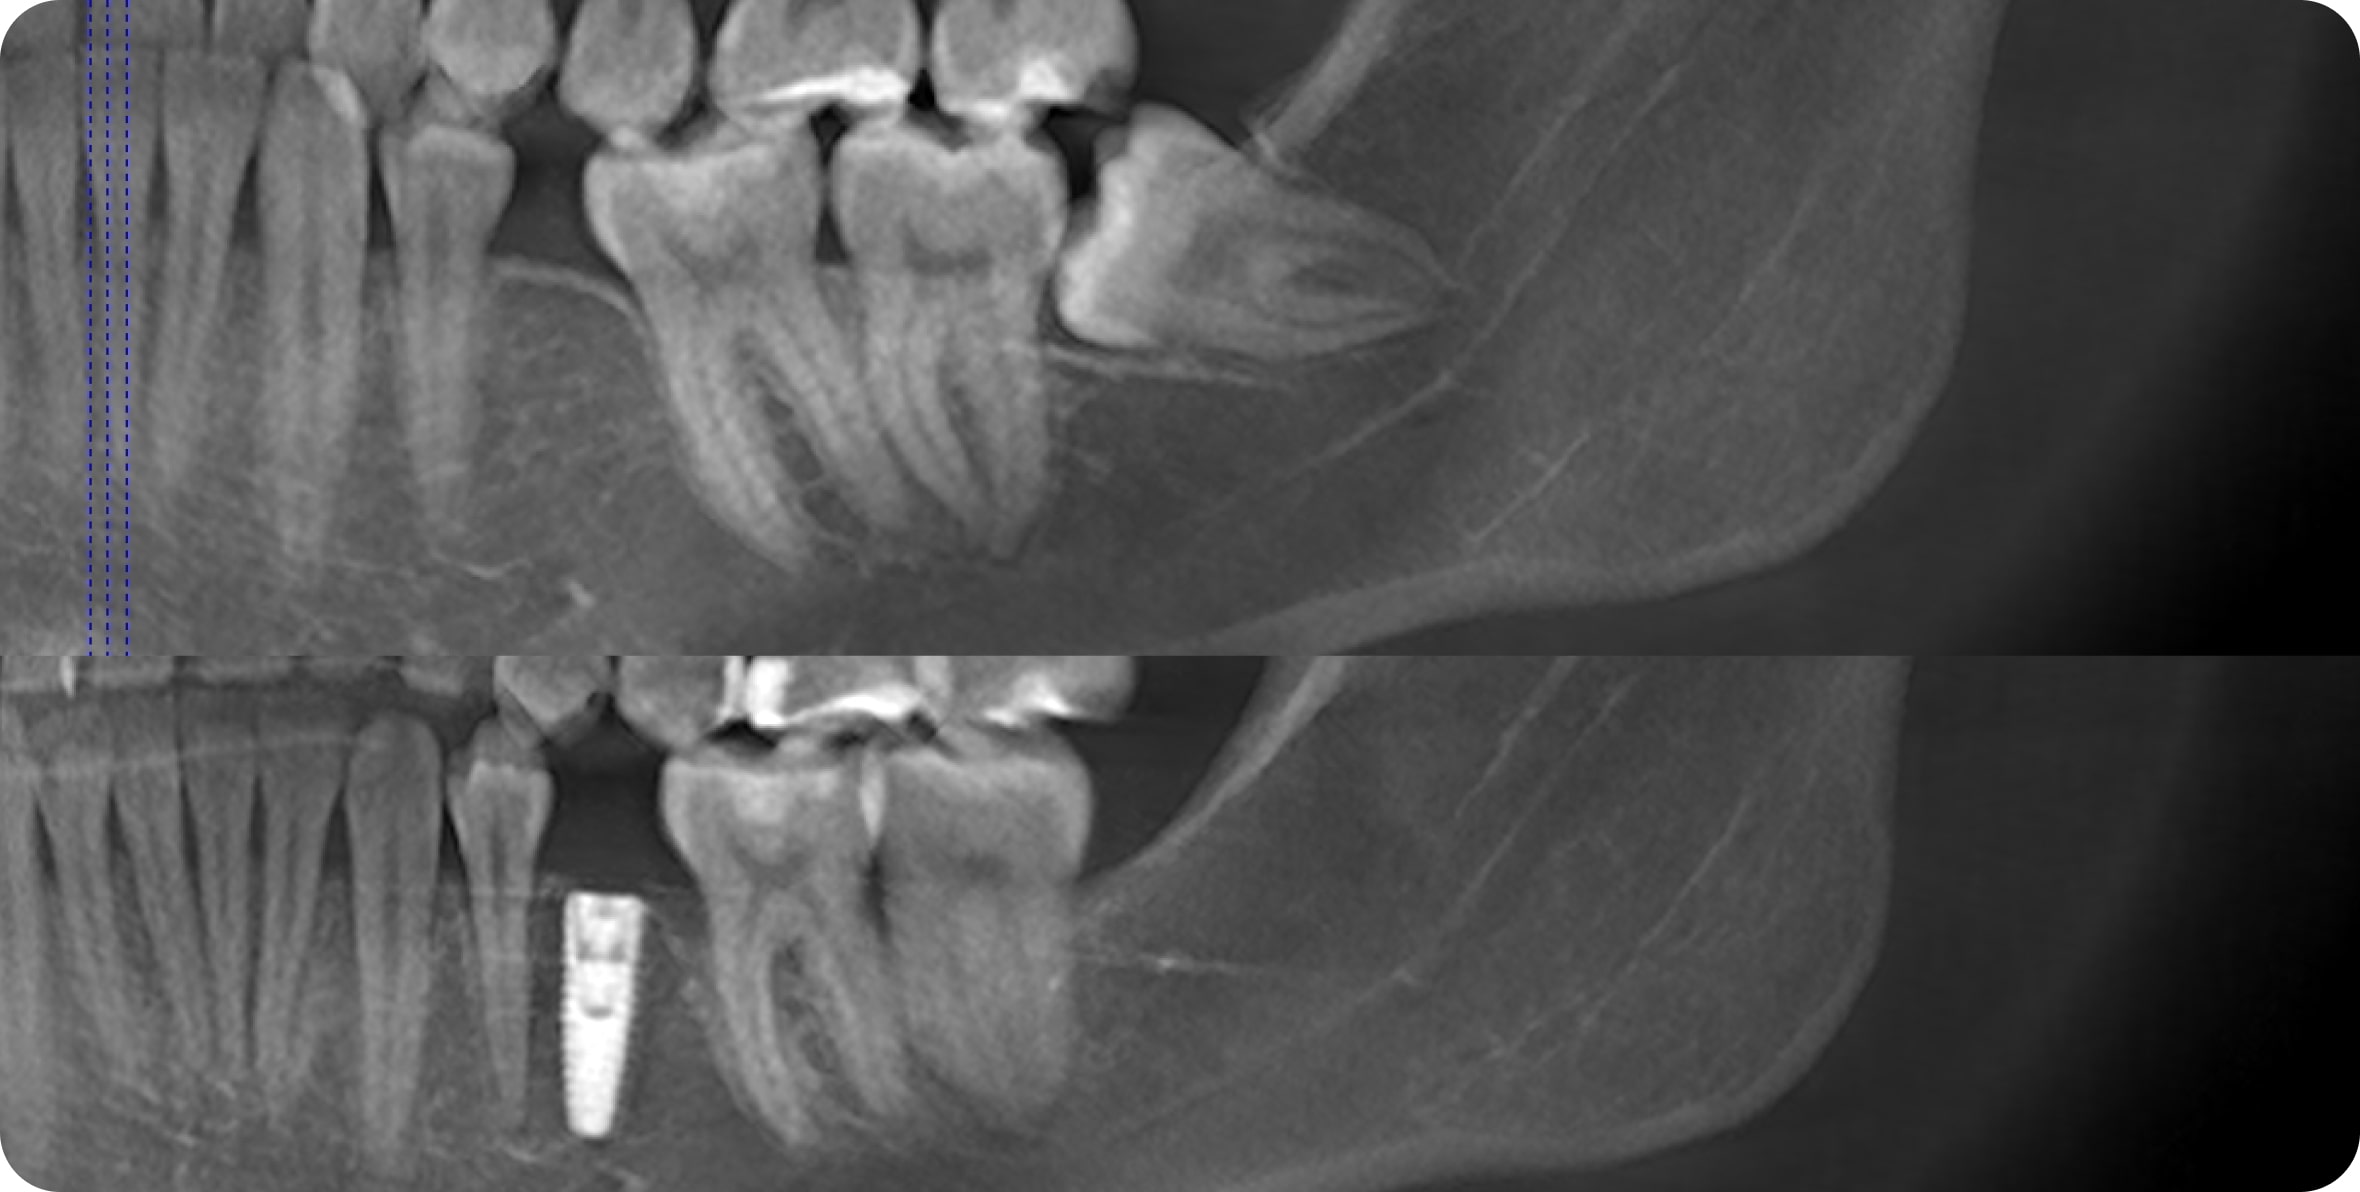

• Компьютерная томография

• Предварительная подготовка (лечение кариеса, удаление зубов мудрости, имплантация)

В 95% случаев мы рекомендуем удалить все 4 зуба мудрости, так как они могут мешать перемещению зубов или искривить зубы после лечения

В редких случаях их можно не удалять. Требуется консультация специалиста

Ортодонтические мини-винты используются как дополнительная опора для перемещения зубов. Винты устанавливаются временно в кость между зубами на 3-6 месяцев